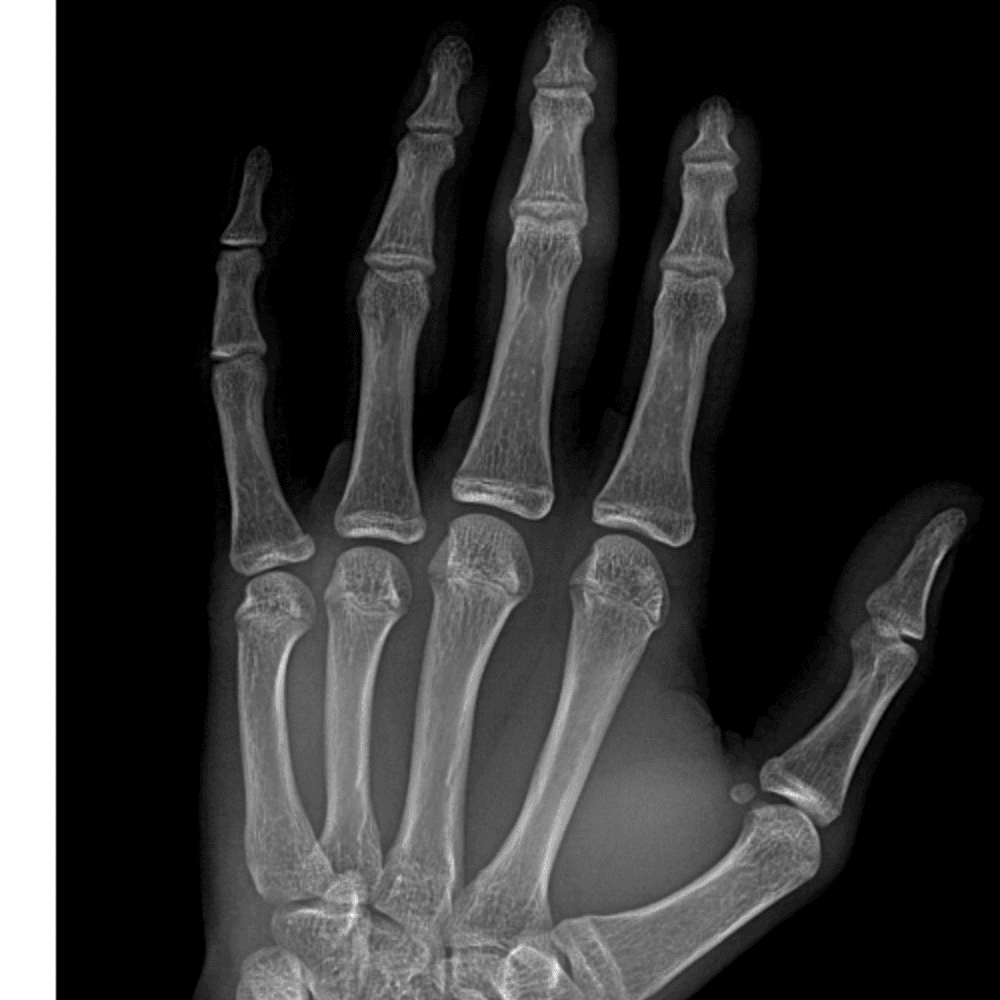

Simulates call by including subtle or difficult cases and some normals.

30 cases